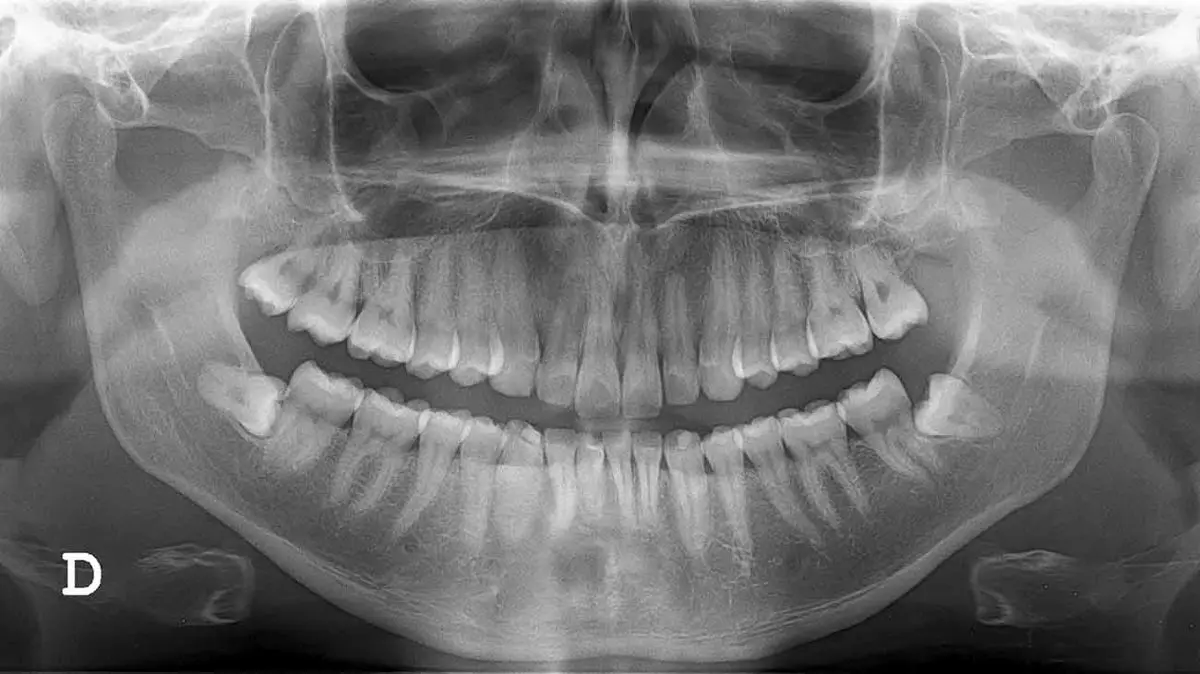

به گزارش رکنا ، از عکس های opg جهت تشخیص دقیق مشکلات فک و دندان ها استفاده می گردد. OPG مخفف کلمه Ortho Pantomo Gram است که کلمه Ortho در آن به واژه ارتودنسی دندان باز می گردد. به وسیله عکس او پی جی می توان موقعیت کلیه دندان ها، عفونت ها، پوسیدگی دندان و کلیه موارد مهم دیگر در دندانپزشکی را مشاهده نمود. این نوع عکس در دسته عکس های رادیوگرافی و رادیولوژی قرار می گیرد.

تصویر برداری opg از نوع اشعه ایکس می باشد. به وسیله پرتو ایکس که توسط دستگاه رادیوگرافی تولید می گردد می توان جزئیات فک بالا و پایین را به صورت واضح مشاهده نمود.